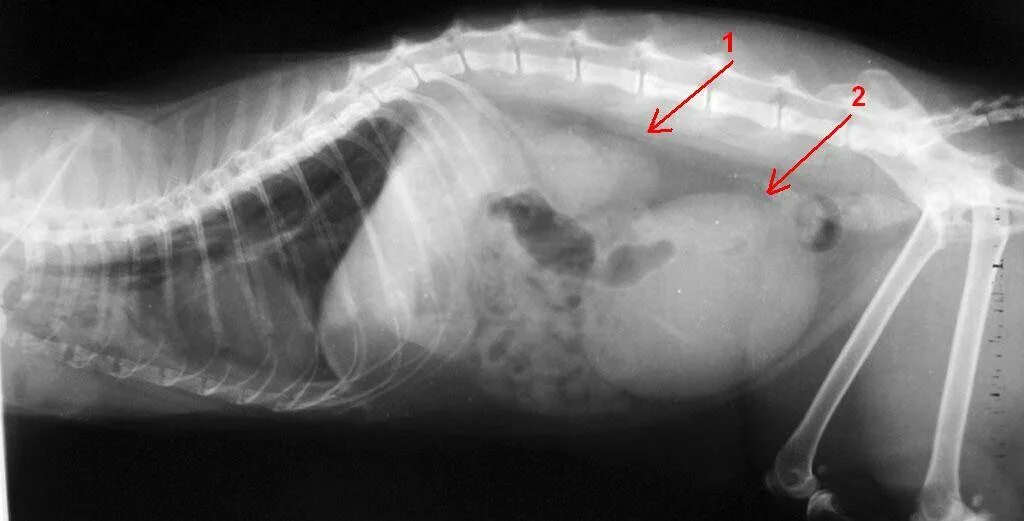

Животные с 1 почкой